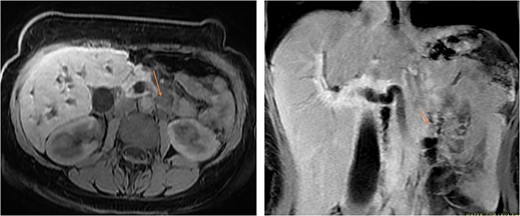

On examination, she looked deeply jaundiced. Her abdominal exam was unremarkable. Her laboratory workup showed a picture of obstructive jaundice with elevated tumor markers, namely, CEA and Ca 19.9. An abdominal CT scan was done and showed diffused intrahepatic and extrahepatic biliary dilation with ectopic insertion of the distal CBD into the distal duodenum. However, no distal CBD stones were seen. But the bulging of the periampullary region, specifically at the upper border of the ampulla, nevertheless, no clearly delineated periampullary mass can be appreciated. Magnetic resonance cholangiopancreatography [MRCP] showed the same finding (Fig. 1).

MRI in axial and sagittal views shows the location of the AOV tumor, as pointed out by the arrows.